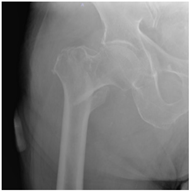

For X-ray 2, four scenarios were developed.![]() | Scenario 1: What would be your operation preference for a mobile patient aged 50–70 and with an ASA score of 1–2? Scenario 2: What would be your operation preference for a mobile patient aged 71 years or older with an ASA score of 1–2? Scenario 3: What would be your operation preference for a mobile patient aged 50–70 with an ASA score of 3–4? Scenario 4: What would be your operation preference for a mobile patient aged 71 years or older with an ASA score of 3–4? |